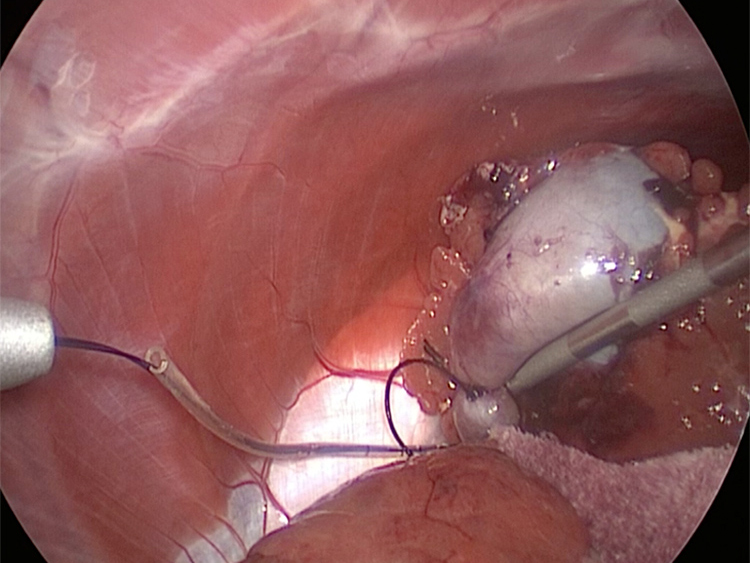

胆嚢の通路がちゃんと開通しているのか調べるために造影検査をしています。 この処置をすることで洗浄の効果と詰まりを確認することができます。

体の外に出すためお腹の中で袋に入れていきます。

このときに胆嚢と一緒にクリップやガーゼも回収します。そしてお腹の中をきれいにしていきます。

胆嚢の頸部に糸を通し動脈を確保しています。

総胆洗浄をして詰まりがないかまずは確認します。

きれいに開通していました。鉗子が大きく感じますが体が小さいので大きく見えます。

胆嚢を少しずつ丁寧に肝臓から剥がしています。